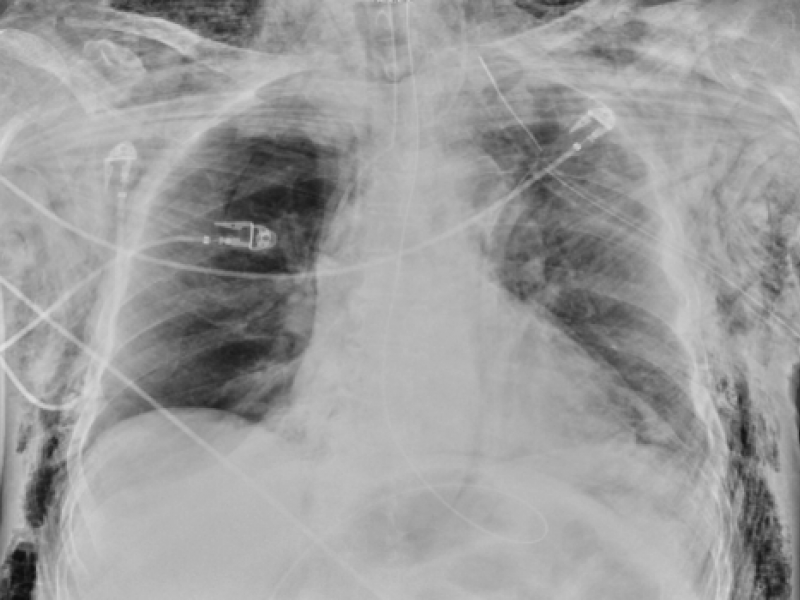

A 55 year old male presents to the ED in respiratory